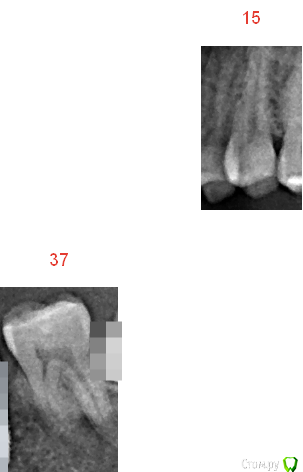

MAKO Опубликовано 4 августа, 2016 Автор Поделиться Опубликовано 4 августа, 2016 Прикладываю снимки этих зубов. Повторюсь, что сейчас ничего не беспокоит, смущает лишь факт, что такое имело место быть дважды и интересует нормально ли это? Ссылка на комментарий

MAKO Опубликовано 9 августа, 2016 Автор Поделиться Опубликовано 9 августа, 2016 Поискал в интернете и в одной из статей нашел следующее:В норме небольшая боль может возникать при нажатии на пломбу, при попадании твердого кусочка пищи на зуб во время еды, при проведении по пломбе ногтем или зубочисткой. Болевые ощущения чаще возникают после лечения глубокого кариеса: дно кариозной полости находится близко к «нерву» зуба, и поставленная пломба при нажатии на нее передает давление на пульпу зуба. Со временем эти болевые ощущения уменьшатся, т.к. пульпа зуба выработает защитный слой дентина и «отгородится» от пломбы. Однако на это требуется определенное время, и неприятные ощущения при накусывании на зуб могут сохраняться до нескольких месяцев. Так как эта статья по всей видимости написана копирайтером, поэтому хотелось бы услышать подтверждение от специалистов. У меня именно так и было, как написано выше. Диагностирован в 15 был глубокий кариес, а в 37 средний. Ссылка на комментарий